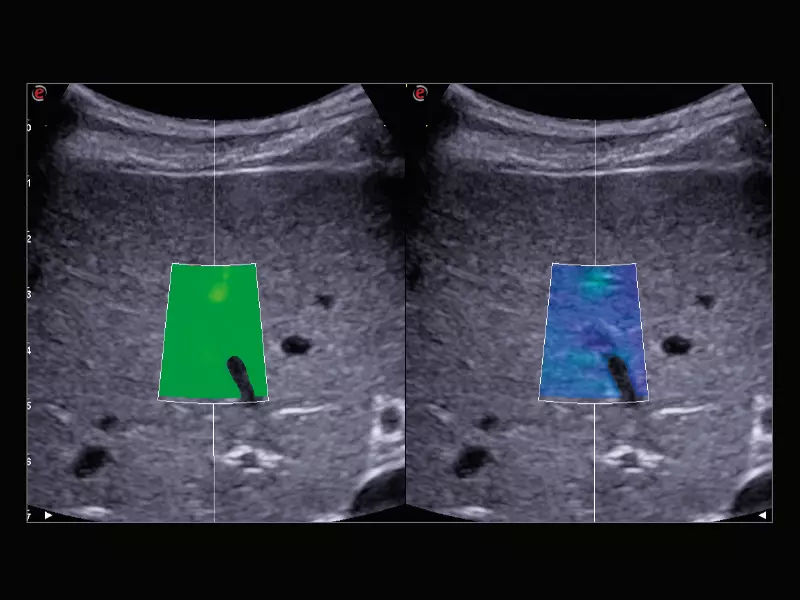

MyLab™C30 - Liver QAI

MyLab™C30 - Liver QAI